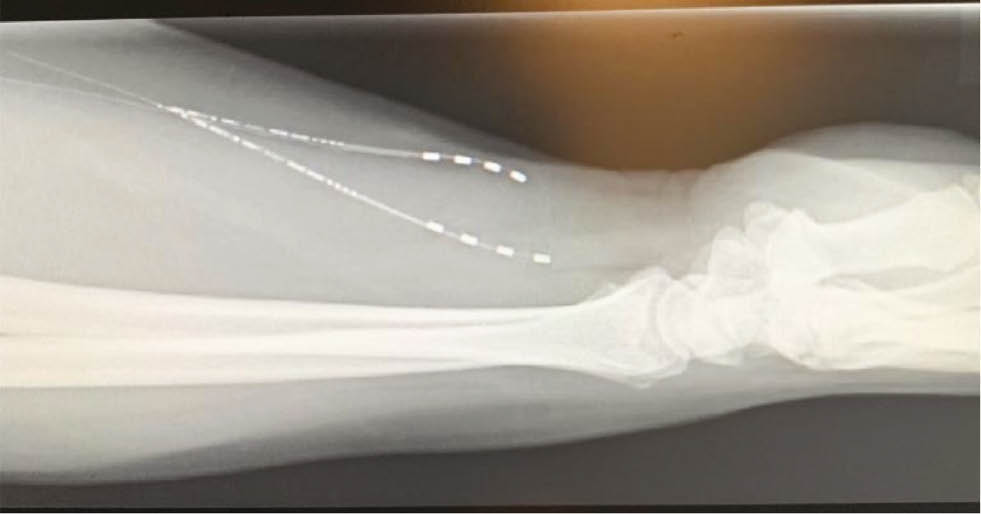

Follow up radiographs of the forearm and hand were obtained to verify the location of the implanted electrodes (Figs. 4 and 5). Both anterior-posterior (Fig. 4) and lateral (Fig. 5) views confirmed appropriate placement of two electrodes along the median and radial nerves.

Fig. 5:

Lateral radiograph of the forearm disclosing the position of the implants at the required anatomical site.